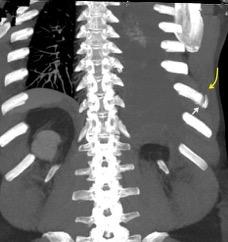

Comunica con el hiato esofágico y el espacio pararrenal anterior.

Colecciones “inflamatorias” abdominales llegan al tórax vía el hiato esofágico o por vía transdiafragmática

Afectación transdiafragmática: 5,6-43,7% de quistes hepáticos. “Área desnuda” del hígado.

Panda A et al. “Straddling Across Boundaries”. Thoracoabdominal Lesions: Spectrum and Pattern Approach. Curr Probl Diagn Radiol. 2015 Área desnuda. El hígado en contacto directo con el tendón central del diafragma. Contiene el hiato de VCI.